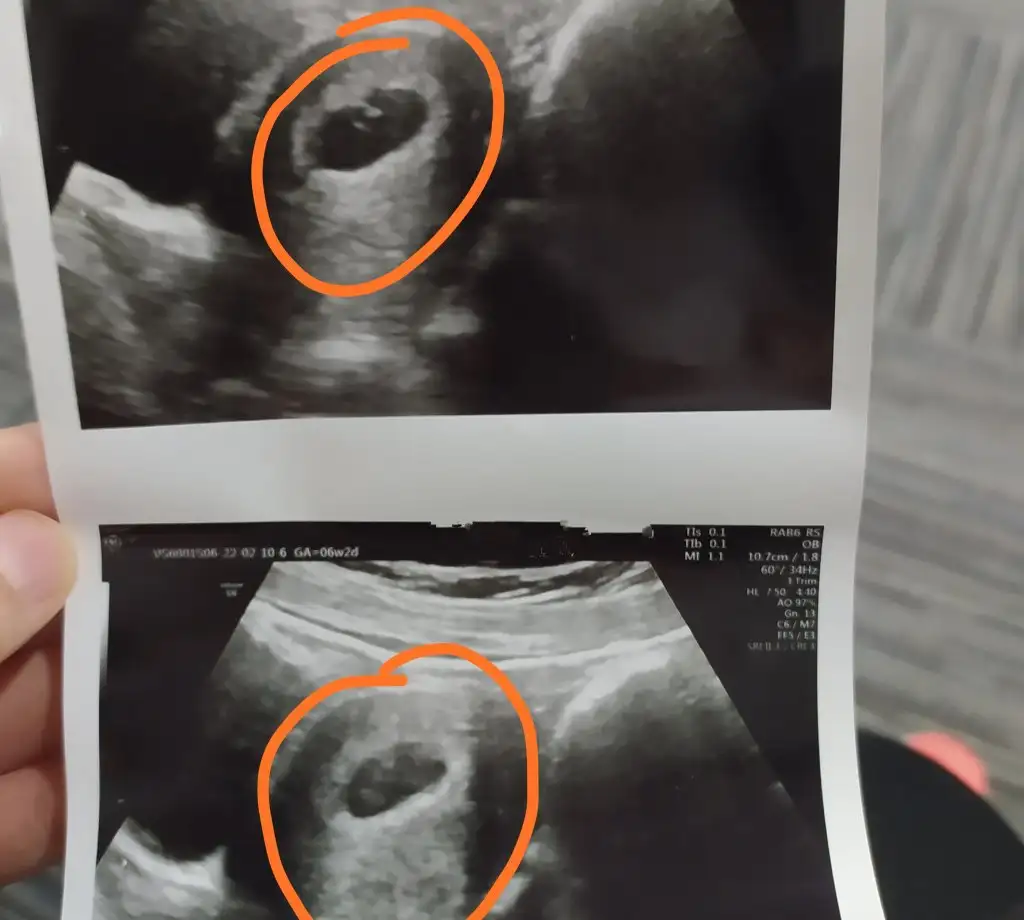

Kızlaaarrr kese içinde minicik bebek 6+2 K kbryummy L lafontaine M Maviay @üççiçekannesi@annekaraca

Ben 5+2 de keseyi gördüm 6+2 yani bugün embriyoyi gördüm uzaktan kalp atışını duydum Dr öyle dedi 🤣 beta çok erken bakıldı benim 26 çıktı adetten üç gün önceydi galiba iki sonrada 80 çıktı dha da başka beta bakılmadi